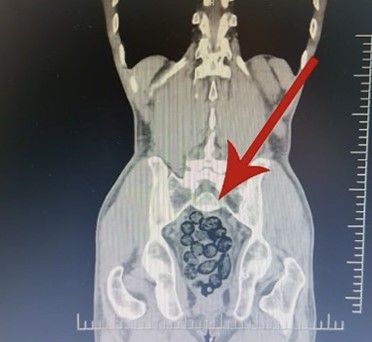

Şüpheli hareketler sergileyen yabancı uyruklu bir yolcunun yapılan tıbbi kontrollerinde, midesinde kapsüllenmiş halde 64 parça uyuşturucu madde olduğu belirlendi.

Toplamda 472 gram metamfetamin yutarak sevkiyat yapmaya çalışan şahıs, midesindeki paketlerin çıkarılmasının ardından gözaltına alındı.